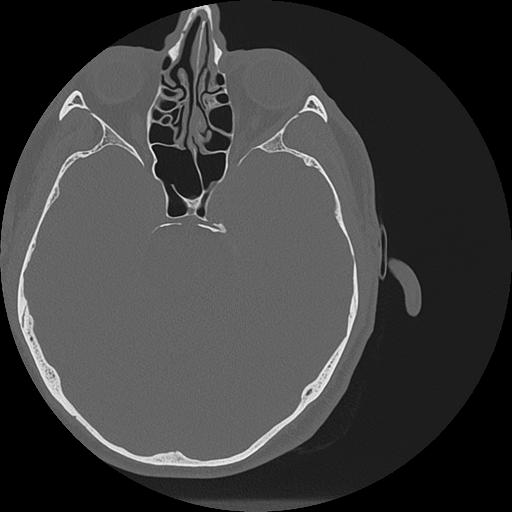

7 HUESO,,Vol,0.5,HUESO,,